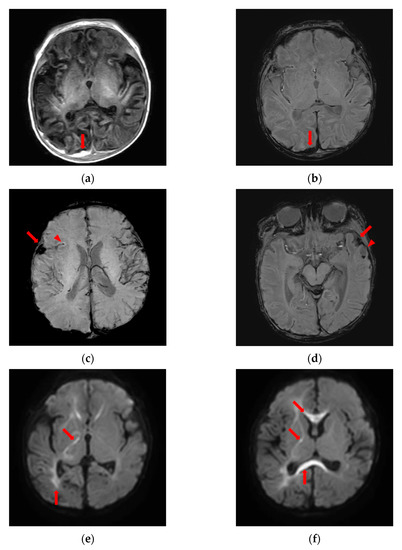

2. Case Presentation